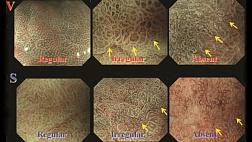

· Больным раком ободочной кишки до начала лечения рекомендуется выполнять колоноскопию с биопсией – наиболее информативное исследование при раке ободочной кишки, позволяющее непосредственно визуализировать опухоль, определить ее размеры, локализацию и макроскопический тип, оценить угрозу осложнений (кровотечения, перфорации), а также получить материал для морфологического исследования. Для получения достаточного количества материала требуется выполнить забор нескольких (3–5) образцов тканей стандартными эндоскопическими щипцами [16, 19, 20].

Комментарии: план лечения не следует составлять до получения данных патолого-анатомического исследования биопсийного материала. При подслизистом инфильтративном росте опухоли возможен ложноотрицательный результат, что требует повторной биопсии. Чувствительность и специфичность метода возрастают при использовании современных технологий эндоскопической визуализации (увеличительной эндоскопии, узкоспектральной эндоскопии, хромоэндоскопии, флуоресцентной диагностики).